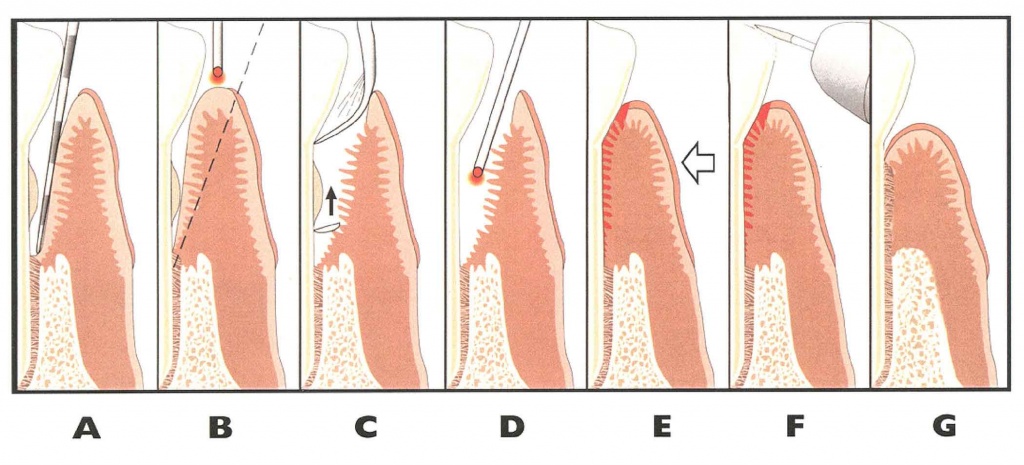

이유가 잇몸과 치아 사이에는 틈이 있는데, 이 틈의 잇몸 선 아래 부분을 박테리아가 공격하여 치주인대와 인접조직을 손상 시키게 되고, 염증이 진행되면 더 많은 조직이 파괴되고 홈이 치주낭으로 발전하게 되며, 치주염이 심할수록 치주낭의 길이가 깊어지게 됩니다.